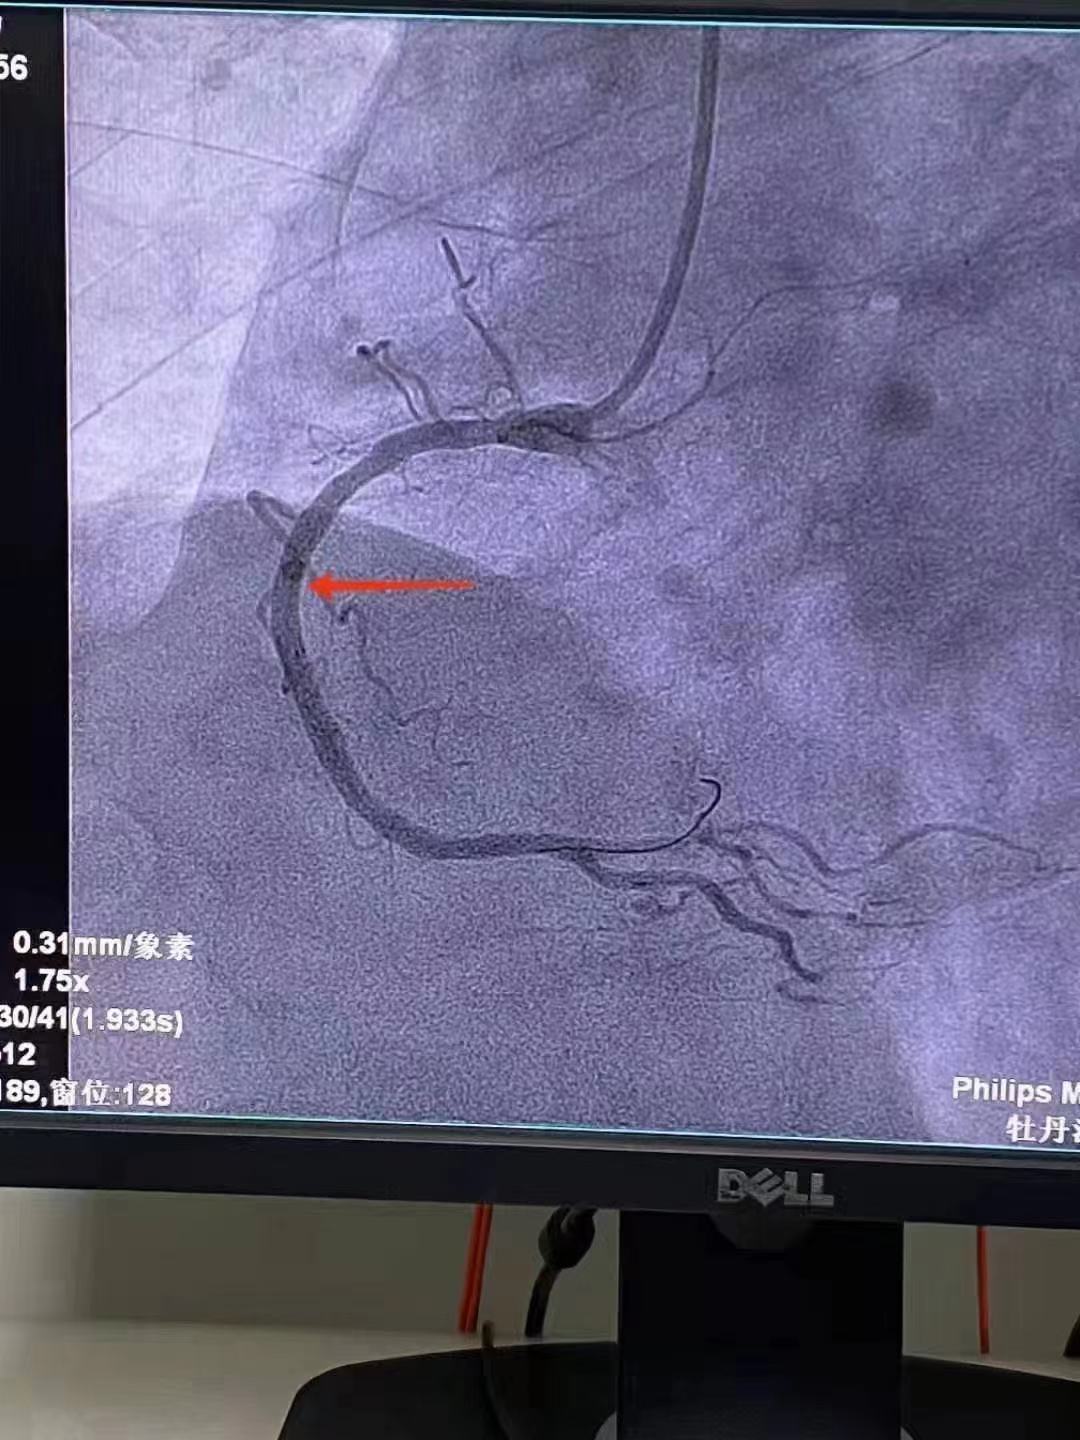

祝賀 牡丹江心血管病醫院關春普 主任團隊成功為患者植入Xinsorb生物可吸收支架!

祝賀 牡丹江心血管病醫院關春普 主任團隊成功為患者植入Xinsorb生物可吸收支架!

祝賀 牡丹江心血管病醫院關春普 主任團隊成功為患者植入Xinsorb生物可吸收支架!